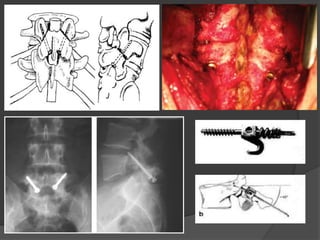

Tratamiento médico  EspondilolistesisTIPO 1, 2 y 3 SDSG  Restricción actividad física  Reposo + AINES  Kinesiología  Ortesis temporarias  >80% efectividad

 Espondilolistesis deAlto Grado - Artrodesis in situ - Descompresión y artrodesis posterior - Reducción artrodesis 360 - Resección de L5 y APL L4 – S1